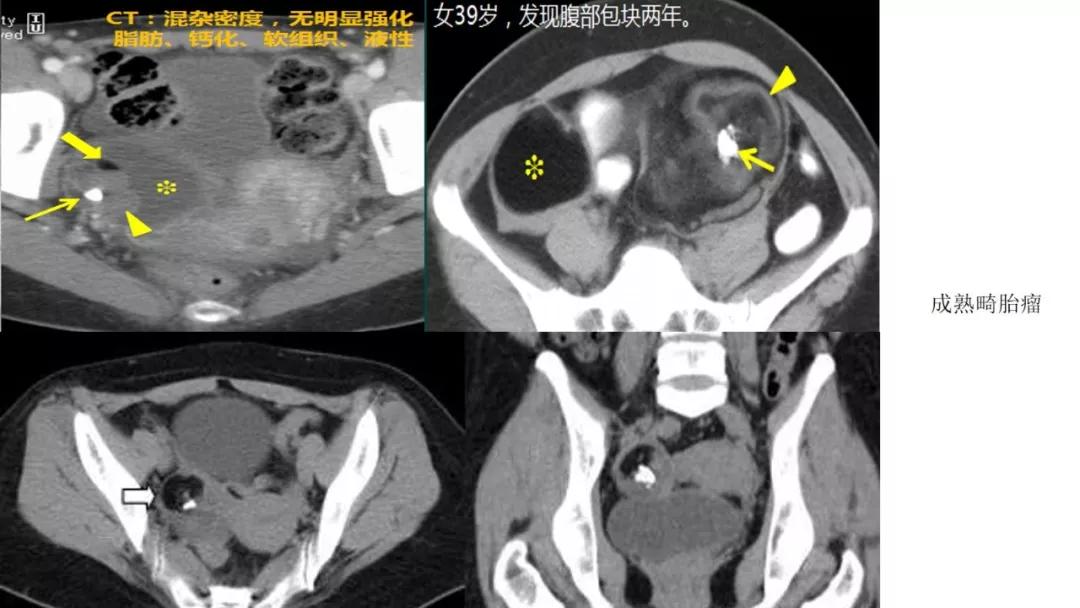

生殖细胞肿瘤占卵巢肿瘤的20%,以成熟畸胎瘤-皮样囊肿多见,良性多,恶性少。表现为囊实性混合性或实性肿块,大多数含有脂肪、钙化等特征。

良性者常呈囊性肿块,脂囊,脂液囊,液囊。少数混合成分,实性。壁光整可稍厚,囊内有脂、液分层现象,多数伴有粗大钙化或骨骼。

出现脂肪:畸胎瘤,囊性为主是成熟、实性为主是不成熟